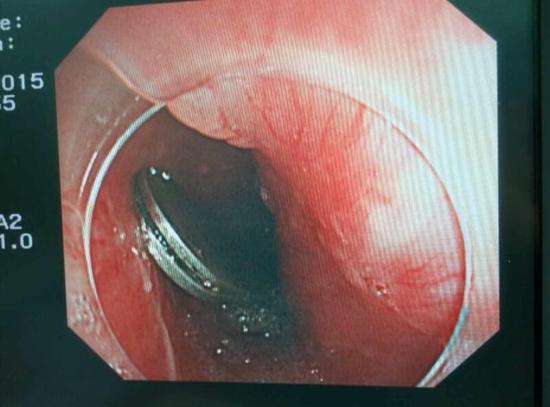

手術(shù)中,范醫(yī)生通過(guò)胃鏡準(zhǔn)確發(fā)現(xiàn)了胃里的鑷子。但讓他驚訝的是,在華先生胃底竟然還躺著三個(gè)被腐蝕了的打火機(jī),打火機(jī)的金屬部件都已經(jīng)不見(jiàn)了。

隨后,范醫(yī)生先用圈套器套取出了長(zhǎng)10厘米的鑷子,再一個(gè)一個(gè)地取出了打火機(jī)。整個(gè)取出過(guò)程小心謹(jǐn)慎而又一氣呵成,只用了不到10分鐘。